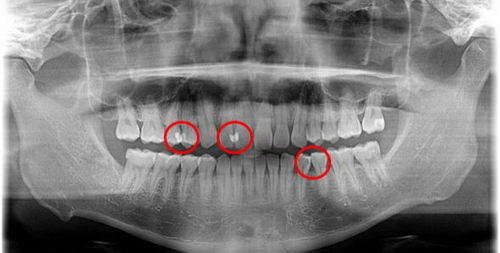

这张图就是牙周炎症导致牙龈退缩,从而出现的黑三角症状。在这种情况下,食物残留很容易发生,所以更加需要彻底地清洁牙齿邻接面,否则出现牙齿松动脱落的几率将会大大增加。